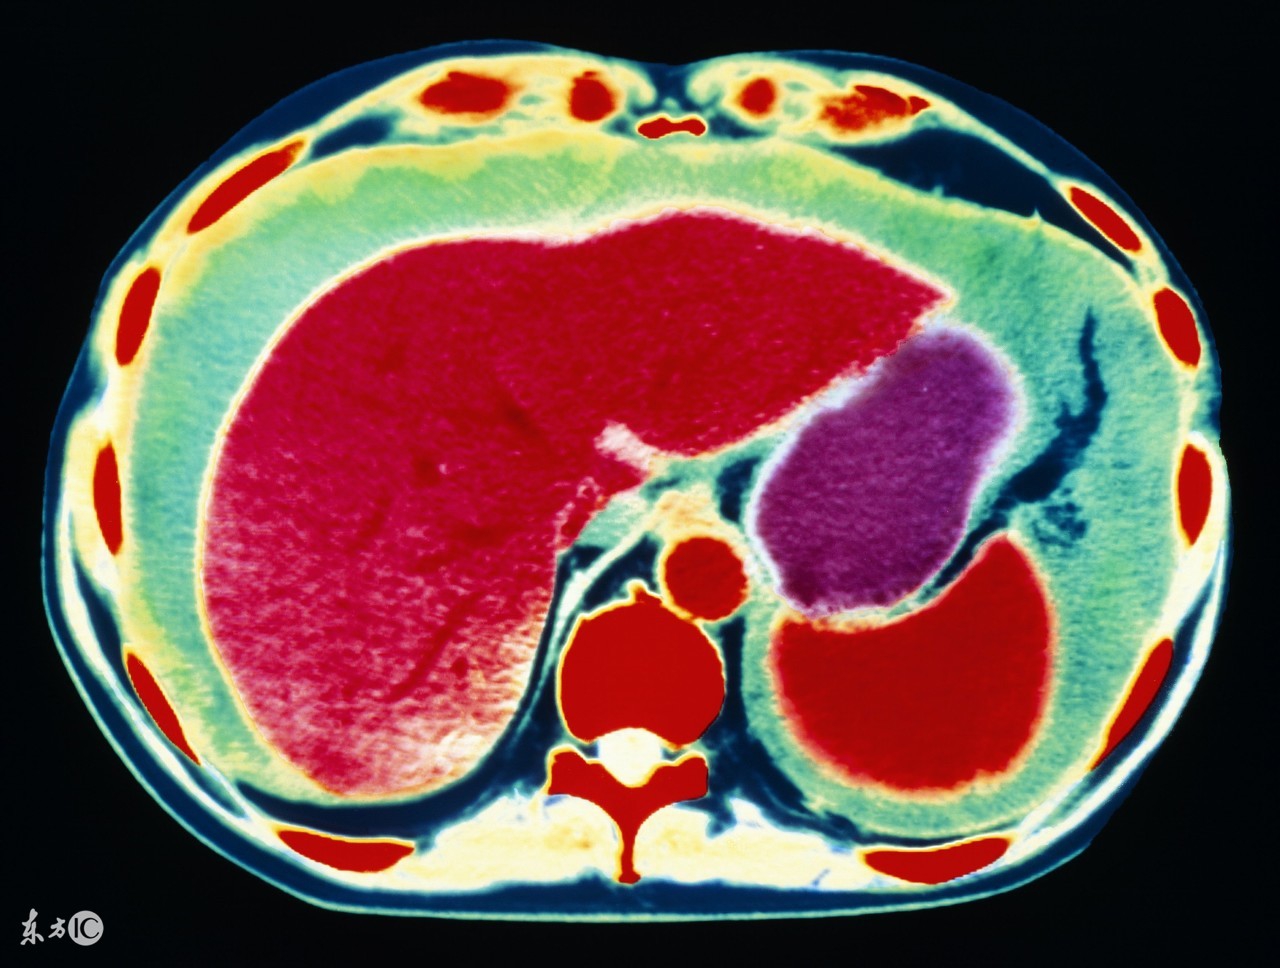

1、肝癌。前面说了,肝病是引起腹水最常见的原因,其中肝癌就是其一。原发性肝癌,发展到一定程度,合并腹水的可能性非常大,其实本质上仍是肝硬化所致,所以肝腹水就是肝硬化腹水。肝硬化时,肝细胞变性、坏死、纤维组织增生,肝内血管床受压、扭曲、变形、狭窄,阻塞了血管,使肝窦淤血,血流量大大降低,门静脉压力升高,同时,毛细血管静脉压力也升高,久而久之,胃肠道、肠系膜、腹膜等血液回流受阻,血管通透性升高,血液中的血浆成分外漏,形成了腹水。肝功能不合,肝脏不能合成白蛋白,低蛋白血症,由于血清白蛋白的降低,血管内胶体渗透压降落,血浆成分外渗而形成腹水。所以,不管什么肝病,到了肝硬化,肝功能不全的阶段,就可能形成腹水。